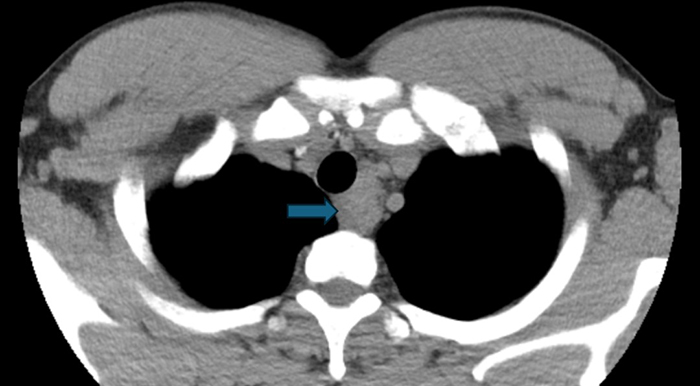

【胸科故事】一根细针揭开纵隔肿物…

一个月前,我收到胸外科同事递来的一张内镜检查申请单:36岁男性,发现“纵隔肿物”。这类患者在我院并不少见,但每一次,我都如履薄冰。打开他的胸部CT,我仔细观察肿物与食管、气管的位置关系——距离够近…